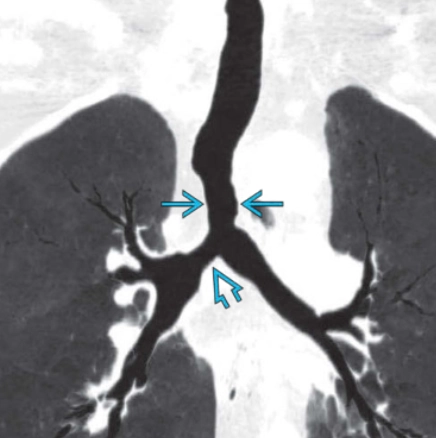

Hẹp khí quản (Tracheal Stenosis)